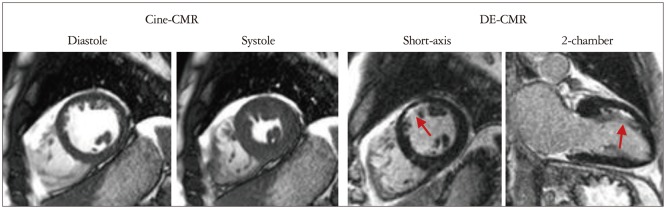

The report by Klem et al.14) demonstrates an example of an interpretation algorithm that uses multiparametric acquisitions to improve diagnostic accuracy. The algorithm is based on 2 principles. First, with perfusion-CMR and DE-CMR, we have independent methods to obtain information regarding the presence or absence of MI. Thus, one method could be used to confirm the results of the other. Second, DE-CMR image quality (e.g., signal-to-noise ratio), is far better than perfusion-CMR since it is less demanding in terms of scanner hardware (DE-CMR images can be built up over several seconds rather than in 0.1 seconds as is required for first-pass perfusion). Thus, DE-CMR is far more accurate for the diagnosis of MI. Conceptually, it then follows that perfusion defects that have similar intensity and extent during both stress and rest ("matched defect") but do not have infarction on DE-CMR are artifactual and should not be considered positive for CAD. Conversely, the presence of infarction on DE-CMR favors the diagnosis of CAD even if the results of perfusion imaging are equivocal. The algorithm and some typical images are dis-played in Fig. 2. Overall, the combination of perfusion and DE images (compared with perfusion images alone) improved the accuracy for the diagnosis of CAD from 68% to 88% in a cohort of patients with intermediate pretest probability of obstructive CAD.

Fig. 2. Interpretation algorithm for incorporating delayed enhancement-cardiac magnetic resonance imaging (DE-CMR) with stress and rest perfusion magnetic resonance imaging (MRI) for the detection of coronary disease. A: Schema of the interpretation algorithm. 1) Positive DE-CMR study: hyperenhanced myocardium consistent with a prior myocardial infarction (MI) is detected. Does not include isolated midwall or epicardial hyperenhancement which can occur in nonischemic disorders. 2) Standard negative stress study: no perfusion defects at stress or rest. 3) Standard positive stress study: perfusion defects are present with adenosine that are absent or reduced at rest. 4) Artifactual perfusion defect: matched stress and rest perfusion defects without evidence of prior MI on DE-CMR. B: Patient examples. Top row: patient with a positive DE-CMR study demonstrating an infarct in the inferolateral wall (red arrows) although perfusion-MRI is negative. The interpretation algorithm classifies this patient as positive for coronary artery disease (CAD). Coronary angiography verified disease in a circumflex marginal artery. Middle row: patient with a negative DE-CMR study but with a prominent reversible defect in the anteroseptal wall on perfusion-MRI (red arrows). The interpretation algorithm classifies this patient as positive for CAD. Coronary angiography demonstrated a proximal 95% LAD stenosis. Bottom row: patient with a matched stress-rest perfusion defect (blue arrows) but without evidence of prior MI on DE-CMR. The interpretation algorithm classifies the perfusion defects as artifactual. Coronary angiography demonstrated normal coronary arteries. Adapted from Klem et al. J Am Coll Cardiol 2006;47:1630-8, with permission of Elsevier.14) LCX: left circumflex artery, LAD: left anterior descending.